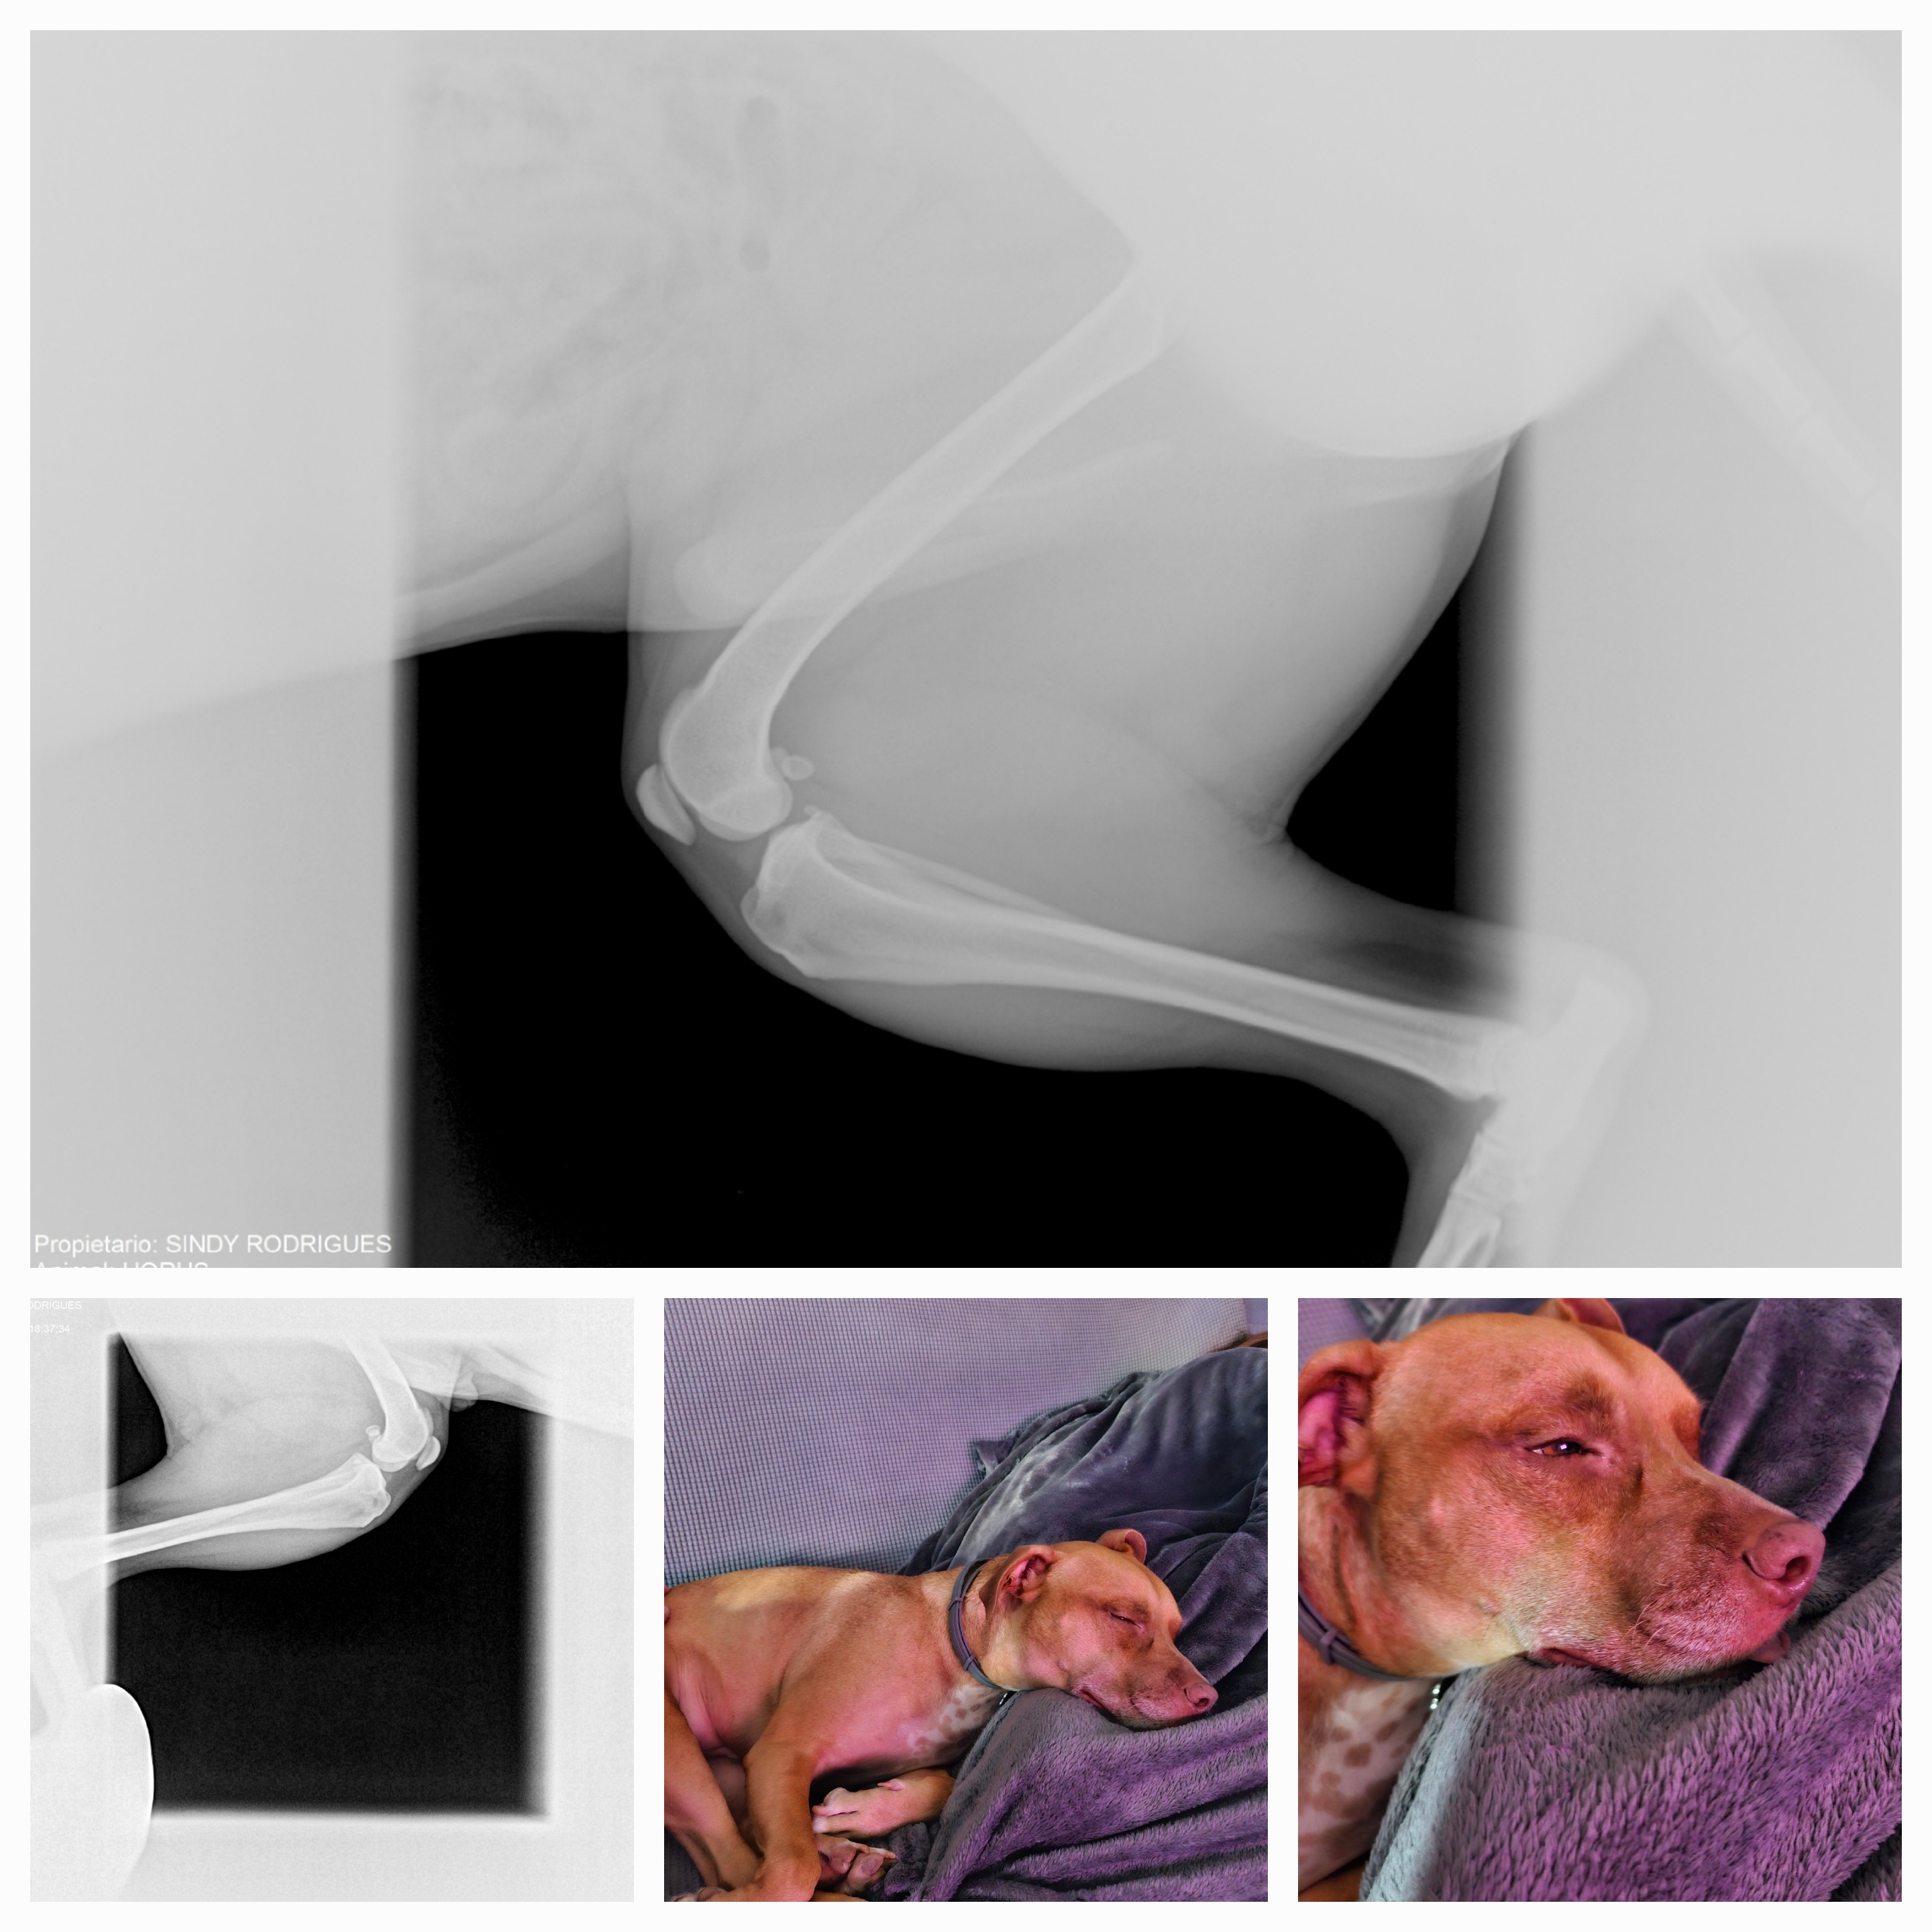

Hola me llamo Horus, he sufrido una ruptura de ligamento cruzado de mi patita izquierda y necesito operarme cuanto antes para no forzar mi otra patita y que no me pase igual, y estoy buscando echar una patita a mis papis para poder hacerlo cuanto antes, gracias a todos a los de buena voluntad.